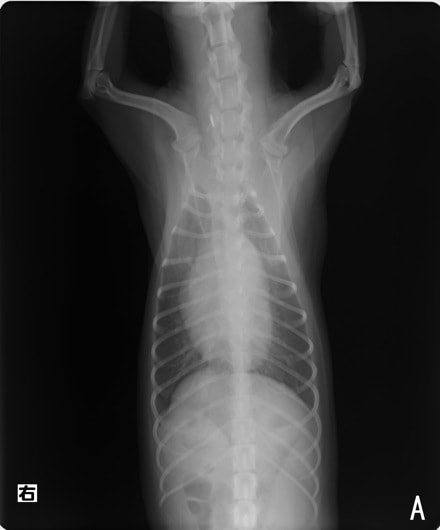

B:胸部レントゲン写真 正面像

左側胸壁心尖部領域を最強点とするLevine 5/6の収縮期性心雑音が聴取された。安静時にも咳が認められる。胸部レントゲン検査において重度の心拡大が及び肺水腫が認められた。超音波検査では、重度の僧帽弁閉鎖不全、三尖弁閉鎖不全が認められた。三尖弁逆流速度から肺高血圧症が示唆された。ACE阻害薬、ピモベンダン、硝酸イソソルビド徐放剤、ベラプロストナトリウム、利尿剤としてフロセミド及びスピロノラクトンを用いて治療を行っている。